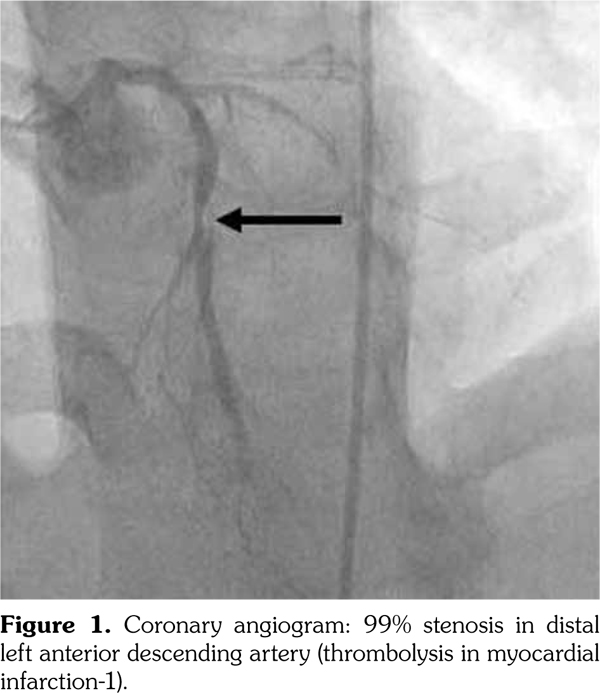

On admission, troponin was 0.05 ng/mL and electrocardiogram revealed sinus tachycardia with peaked T-waves in leads I, aVL, and V5-V6; and inverted T-waves in leads III and aVF. Echocardiogram demonstrated left ventricular hypertrophy with an ejection fraction of 55%. Selective coronary angiography (Figure 1) disclosed a 70% stenosis of the left internal mammary artery graft to the left anterior descending coronary artery and a 99% stenosis in the distal left anterior descending artery. Patient was treated with coronary angioplasty and two drug-eluting stents, reducing stenoses to 0% per final angiography (Figure 2).